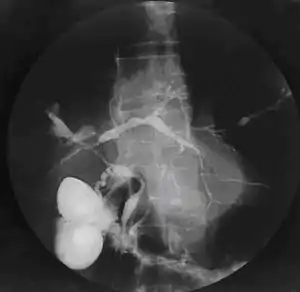

| Cholangiogram of primary sclerosing cholangitis. | |

Historically, a cholangiogram would be obtained via endoscopic retrograde cholangiopancreatography (ERCP), which typically reveals "beading" (alternating strictures and dilation) of the bile ducts inside and/or outside the liver. Currently, the preferred option for diagnostic cholangiography, given its noninvasive yet highly accurate nature, is magnetic resonance cholangiopancreatography (MRCP), a magnetic resonance imaging technique. MRCP has unique strengths, including high spatial resolution, and can even be used to visualize the biliary tract of small animal models of PSC.[19]